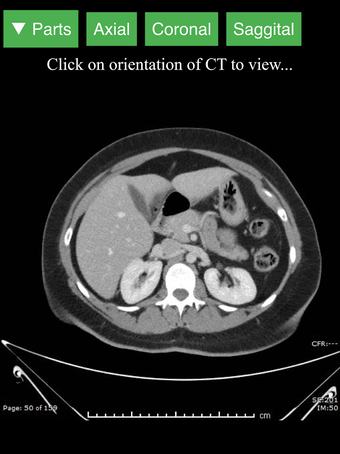

Radiology CT Viewer - полезный инструмент для врачей, медицинских студентов, радиологических техников и других медицинских специалистов, которые хотят узнать больше о человеческом теле и его анатомии. Приложение содержит подробные сечения наиболее важных частей тела. Кроме того, оно содержит интерактивную 3D-модель, которая позволяет вращать, увеличивать и перемещать камеру вокруг изображения, чтобы получить лучший обзор анатомии.

Если вы ищете инструмент, который поможет вам узнать больше о человеческом теле, Radiology CT Viewer - отличный выбор. Он содержит подробные иллюстрации и интерактивную 3D-модель.